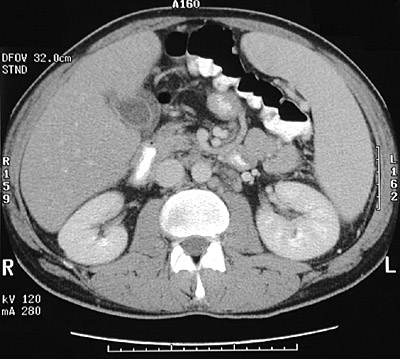

| The gallbladder in this abdominal CT scan revealed a thickened wall with edema fluid as a consequence of acalculous cholecystitis. This patient also had HIV infection, and possible opportunistic infections causing cholecystitis and cholangitis include cytomegalovirus and cryptosporidiosis. Note that there is also marked lymphadenopathy as well as splenomegaly. |